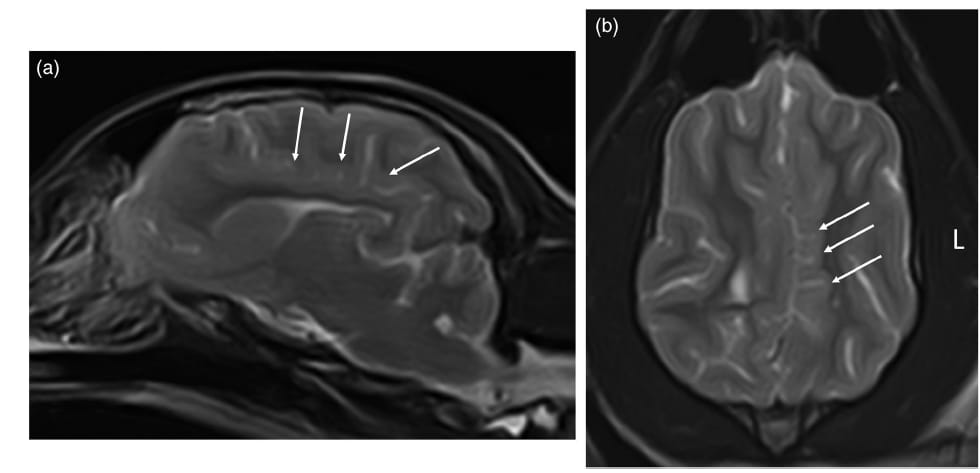

MRI revealed abnormal sulci and gyri in the splenial and cingulate regions of the brain, causing mass effects on the corpus callosum and lateral ventricles. SWI identified asymmetrical abnormal vessels in the occipital lobe, a novel finding in canine PMG studies. White matter in affected regions was underdeveloped, with no perilesional edema. The CSF analysis showed no abnormalities. Despite MRI evidence of brain malformation, the dog's vision and other neurological functions were intact, with seizures being the only clinical manifestation.

(a) Sagittal T2-weighted and (b) dorsal T2-weighted MRI images. The arrows indicate the abnormal gyri and sulci at the splenial